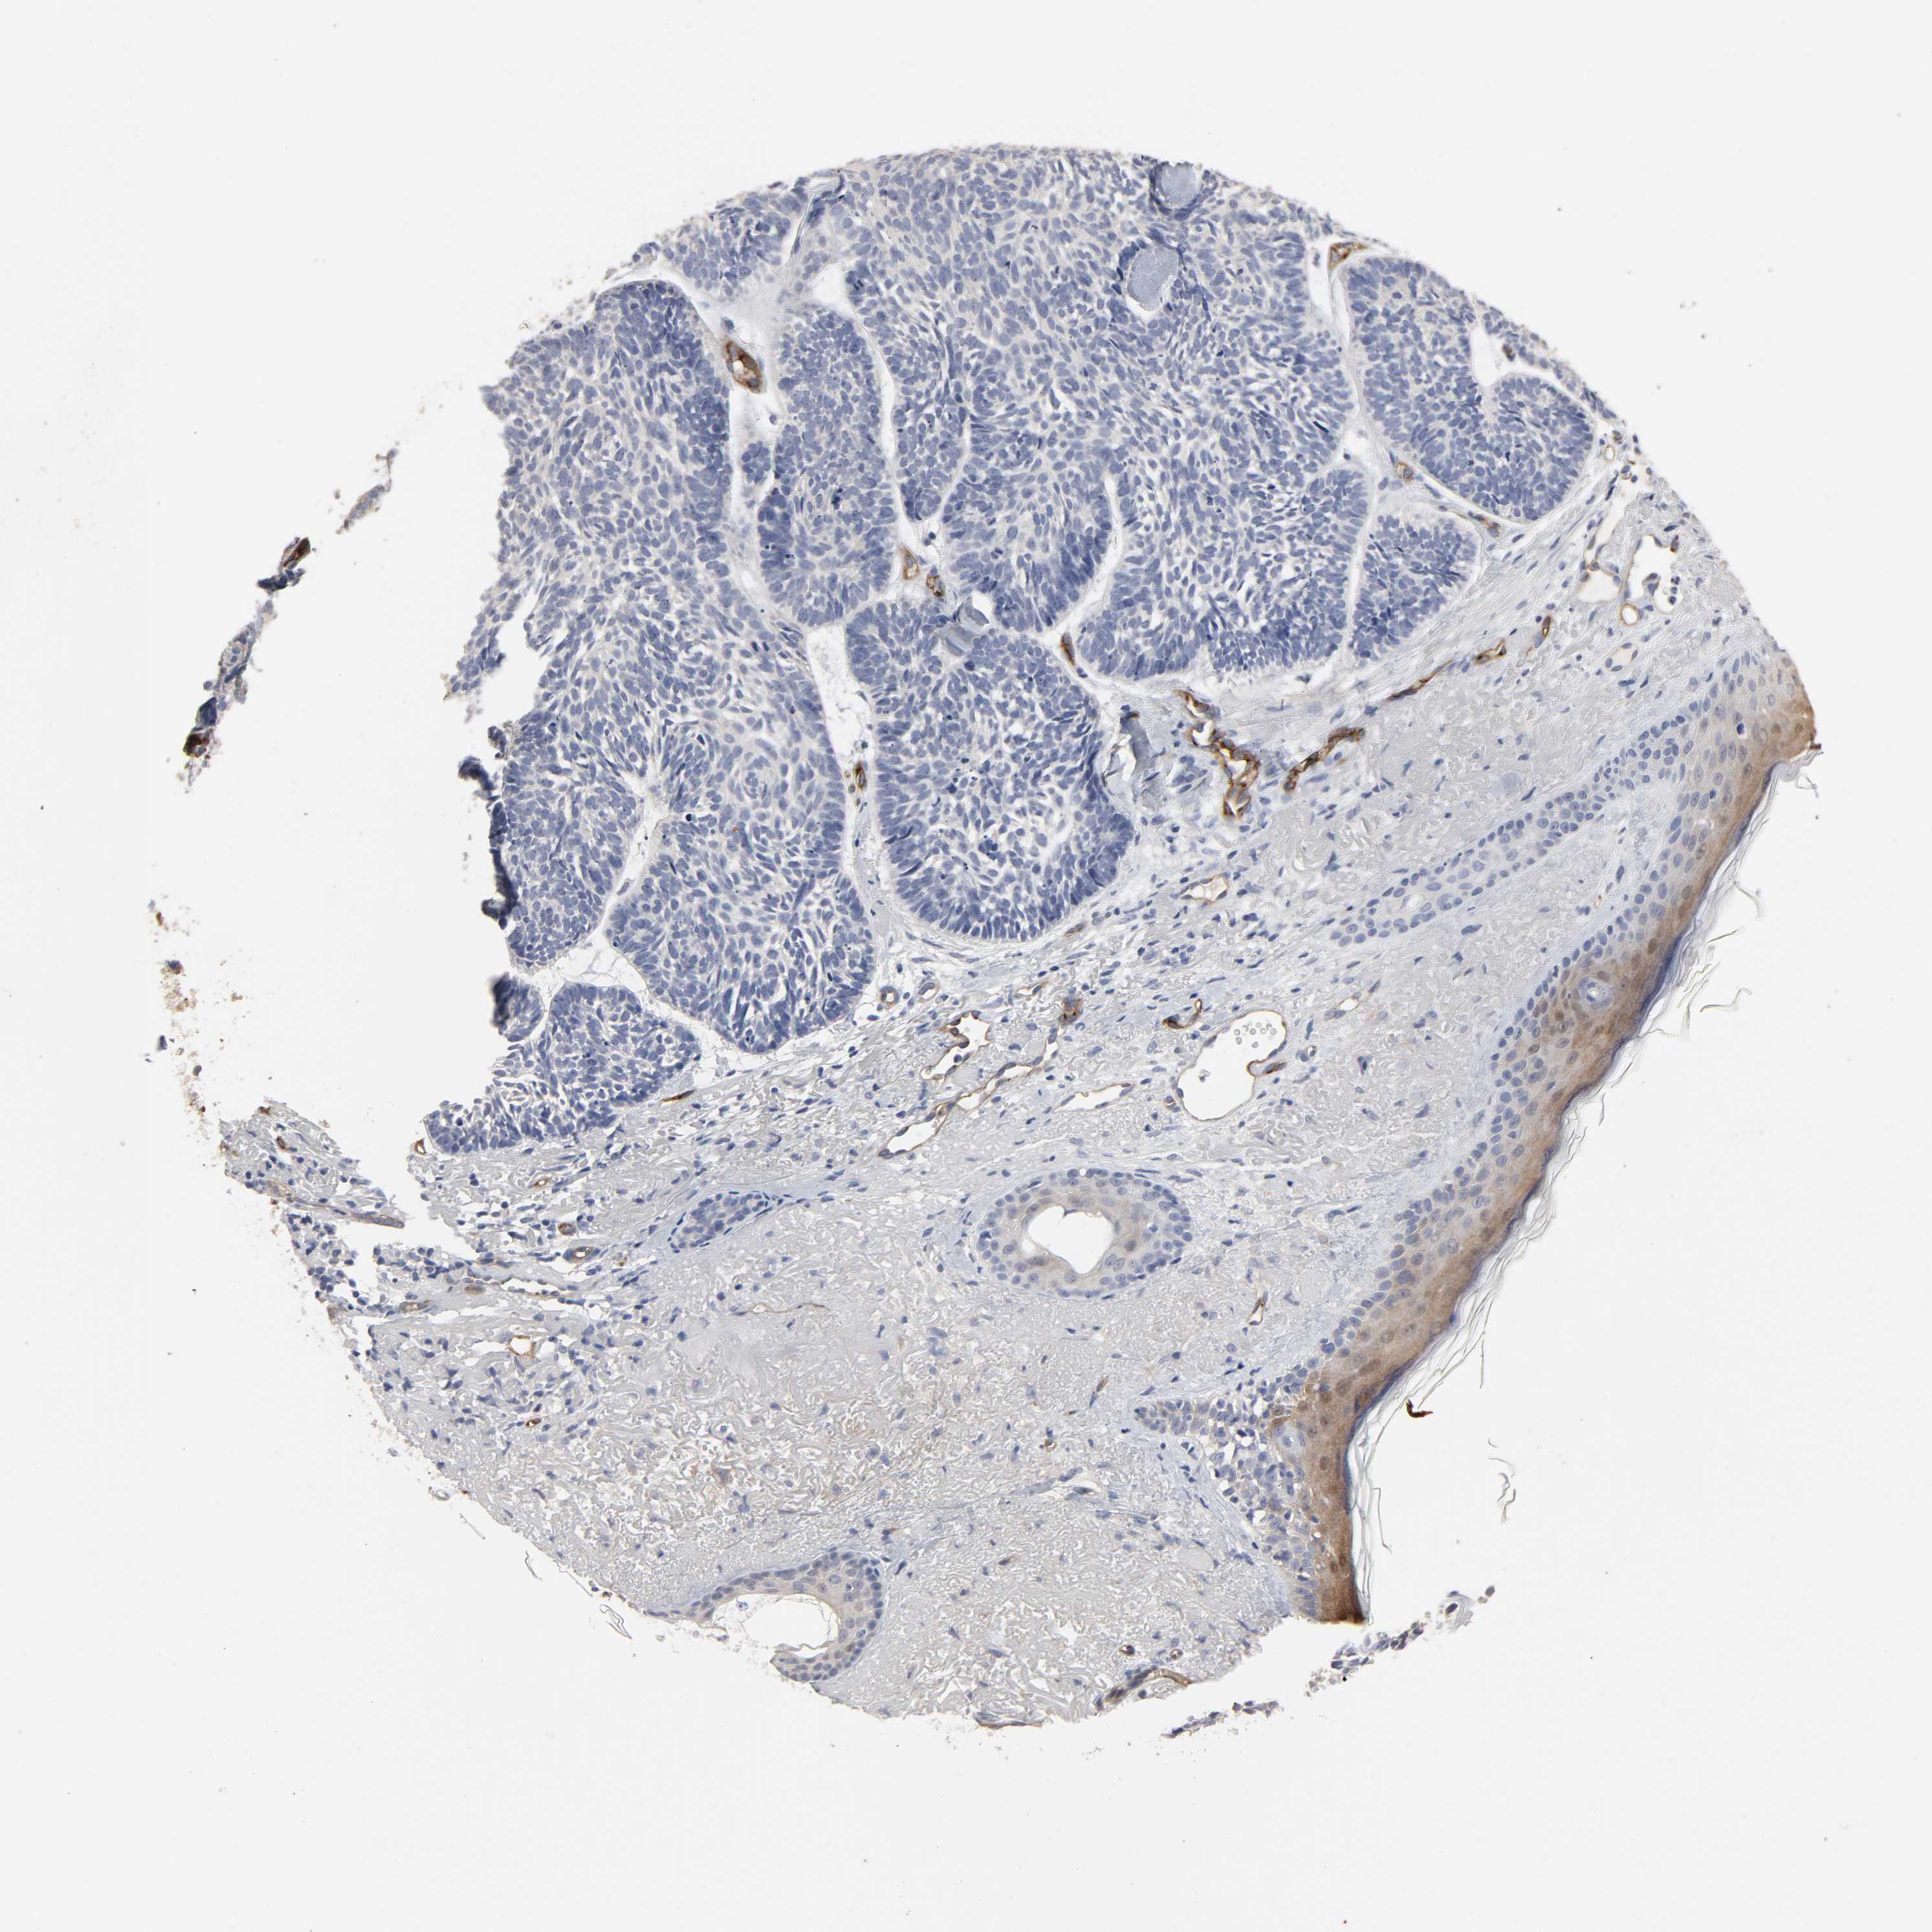

SKIN CANCER - Protein expressioni

A mouse-over function shows sample information and annotation data. Click on an image to view it in a full screen mode. Samples can be filtered based on level of antibody staining by selecting one or several of the following categories: high, medium, low and not detected. The assay and annotation is described here.

Antibody stainingi

Antibody staining in the annotated cell types in the current human tissue is reported as not detected, low, medium, or high, based on conventional immunohistochemistry profiling in selected tissues. This score is based on the combination of the staining intensity and fraction of stained cells.

Each image is clickable and will lead to virtual microscopy that enables deeper exploration of all samples and also displays staining intensity scores, fraction scores and subcellular localization as well as patient and tissue information for each sample.

Antibody CAB004028

Staining

High

Medium

Low

Not detected

Intensity

Strong

Moderate

Weak

Negative

Quantity

>75%

75%-25%

<25%

None

Location

Nuclear

Cytoplasmic/membranous

Cytoplasmic/membranous,nuclear

Squamous cell carcinoma, NOS

Basal cell carcinoma